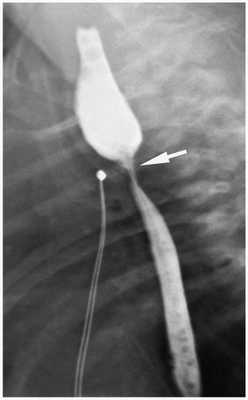

(Справа) Рентгенограмма новорожденного с ассоциацией VACTERL с орога-стральной трубкой, изогнутой в месте АП. Дистальный отдел трахеопищеводного свища отвечает за наличие газа в кишечнике. Аномалии позвонков и расширенные петли кишечника из-за атрезии анального отверстия. Также видны аномалии ребер.

Этот рентгеновский снимок показывает аномалии, относящиеся к ассоциации VACTERL (вертебральные аномалии, атрезия заднего прохода, пороки сердца, трахеопищеводный свищ, атрезия пищевода, почечные аномалии, аплазия лучевой кости и аномалии конечностей). Обратите внимание на аномалию сегментации позвоночника (указатель белого цвета), кишечную трубку, свернутую в атретическом проксимальном участке пищевода (указатель черного цвета), содержащийся в кишечнике газ, связанный с атрезией пищевода и с трахеопищеводным свищом, и деформацию левой верхней конечности.

На обследовании выполняются рентгеновские снимки грудной клетки и брюшной полости, предварительно в пищевод устанавливают рентген-контрастный зонд. Исследование проводится в прямой проекции в вертикальном положении ребёнка. Оценивают уровень стояния зонда (свёрнутый зонд в слепом верхнем сегменте); газонаполнение желудка и кишечника (при наличии трахео-пищеводного свища между нижним сегментом и трахеей будет определяться воздух в брюшной полости, при отсутствии воздуха в желудке и кишечнике исключается наличие нижнего трахеопищеводного свища).

Также проводится рентген-контрастное исследование. Через зонд в верхний сегмент пищевода вводится не более 1 мл контраста. При наличии верхнего трахеопищеводного свища, кроме пищевода окрашивается ещё и трахеобронхиальное дерево.